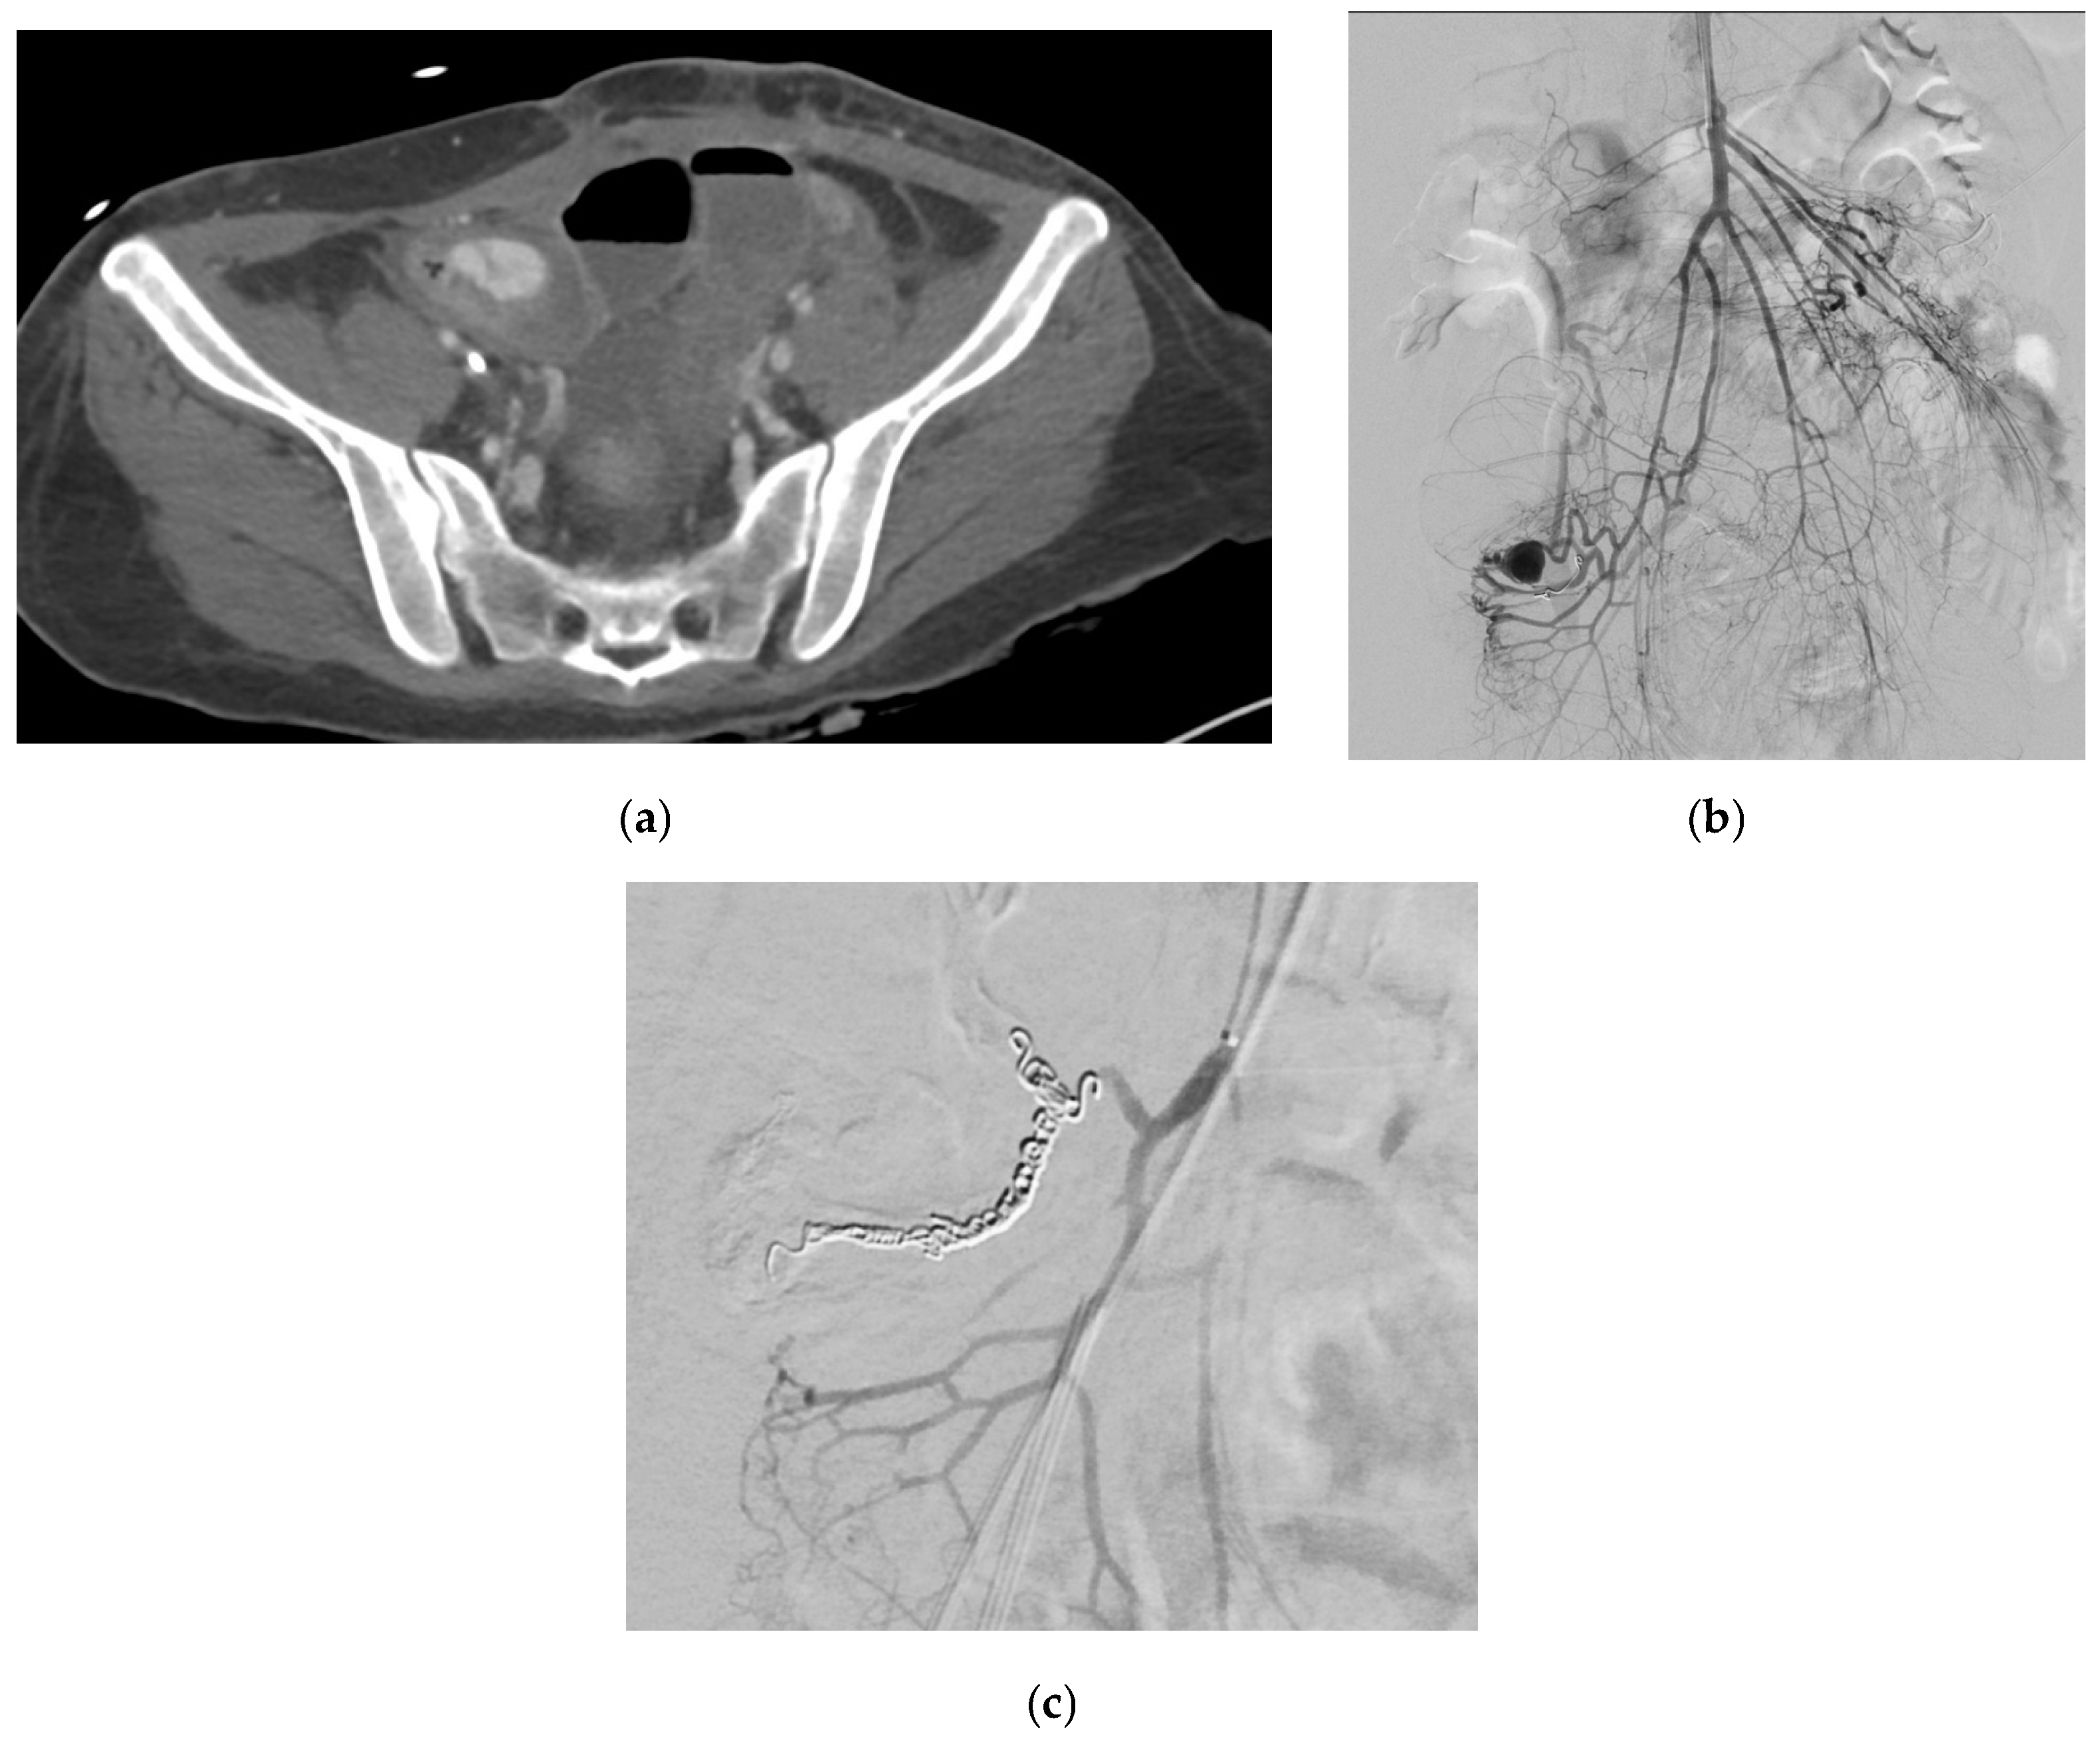

- Madhusudhan, K.S.; Gamanagatti, S.; Gupta, A.K. Endovascular embolization of pseudoaneurysm of left colic artery developing after renal biopsy. Indian J. Nephrol. 2015, 25, 242–245. [Google Scholar] [CrossRef] [PubMed]